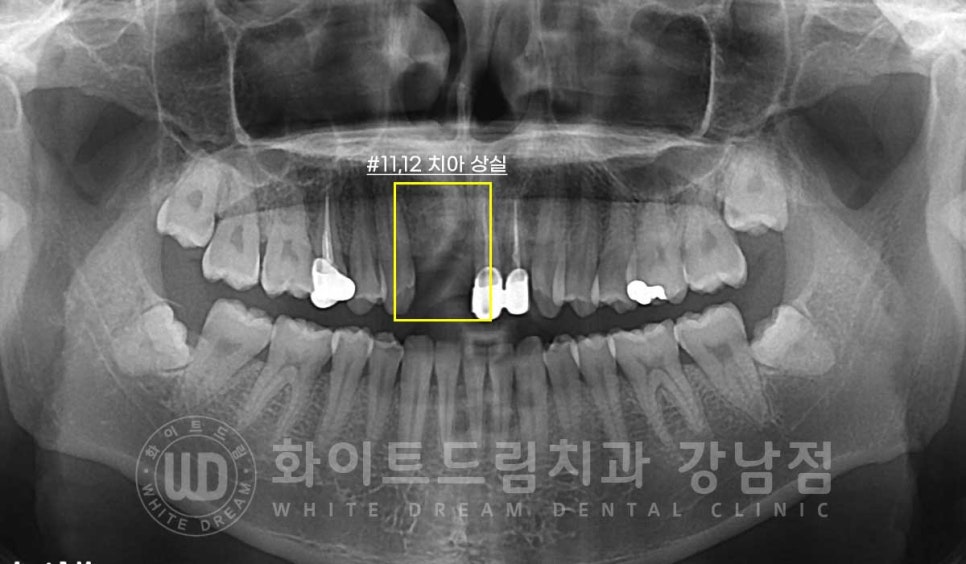

문제가 있던 치아를 발치한 후 임플란트를 식립한 건 아니고

기존 임플란트가 부러져 6개월 전에 제거를 하신 분의 재치료 케이스입니다.

타치과에서 10년 전에 식립한 임플란트가 젓가락을 씹었다고 부러져

제거한 후 한동안 방치를 하신 환자분입니다.

잇몸뼈의 흡수가 조금 진행되어 있어 뼈이식을 동반하여 임플란트를

다시 식립하기로 했고

기존의 오래된 옆 21, 22번 크라운도 함께 교체하여 심미성을 회복한 case입니다.